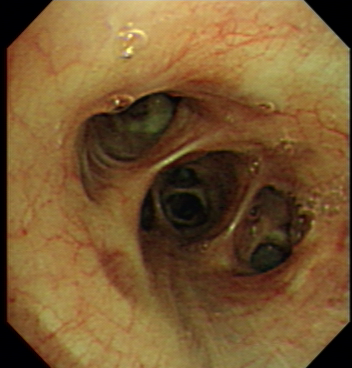

Figure 7: A cancer case was misclassified as a normal case (a), a normal case was misclassified as a cancer case (b), a TB case was misclassified as a cancer case(c)

Figure.  7 shows examples of misclassified cases. Figure. 7a indicates a cancer case that has pale mucosa and yellow secretion and was mis-classified as a normal case by CAD, while Figure. 7b indicates a normal case that has smooth red mucosa and was mis-classified as a cancer case by CAD. Figure. 7c. indicates a TB case that has a round nodule with smooth mucosa and was mis-classified as a cancer case by CAD. Mucosa color, secretions and smoothness are important features for cancer discrimination. In cancer cases, the tumor mucosa is pale, rigid and has dirty secretion. The mis-classification in Figure. 7 might be due to a small dataset for training. Larger training set would extract more minor mucosa features to avoid such mis-classification.